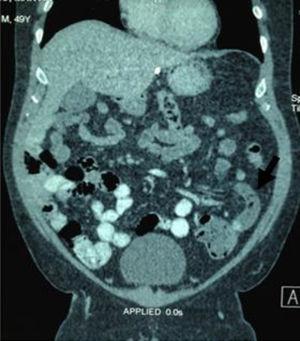

A 49-year-old man had a history of morbid obesity, laparoscopic gastric band placement, and pulmonary thromboembolism 7 years earlier. He came to the emergency service complaining of 24-h progression of sudden, colicky, generalized abdominal pain predominantly in the left lower quadrant, abdominal distension, nausea, and pasty stools. Physical examination showed him to be afebrile, dehydrated, with important abdominal distension, reduced peristalsis, involuntary muscle resistance, and pain upon palpation and decompression of the left iliac fossa. His biochemical parameters were: leukocytes of 9.7 103/ml, neutrophils of 70%, hemoglobin of 17.2g/dl, hematocrit of 52.7%, and platelets of 449 103/ml. Blood chemistry, serum electrolytes, and urinalysis were normal. Initial diagnostic suspicion was diverticular disease. An abdominal computed tomography scan revealed a probable sigmoid volvulus vs colonic malrotation. A barium enema was then carried out that confirmed colonic malrotation (fig. 1). In a new analysis of the tomography scan, acute appendicitis was identified (fig. 2), with a delay in the diagnosis and treatment of approximately 8hours. Laparoscopic appendectomy was performed, washing the abdominal cavity and placing drains. The findings were perforated appendicitis in the left iliac fossa and generalized purulent peritonitis. The patient's progression was adequate and he was released from the hospital on the 4th postoperative day. The histopathologic study confirmed perforated acute appendicitis.

Different cases of appendicitis with atypical location have been described, and the same as in our case, initial diagnosis is often incorrect, delaying diagnosis and treatment. Abdominal tomography provides sufficient information for the surgical plan. It is not necessary to perform dynamic studies to evaluate intestinal malrotation. The typical tomographic findings in malrotation are: duodenal-jejunal junction on the right side, colon on the left side, and an abnormal orientation of the mesenteric vein and artery.1,2,5,6The treatment options for left-side appendicitis are the same as those in cases of its habitual location, and open or laparoscopic appendectomy can be performed.9 The laparoscopic approach is viable with good results. It is also useful for evaluating the differential diagnoses and resolving different pathologies.9,10 With respect to the treatment of intestinal malrotation, there is still no consensus on the asymptomatic patient.6